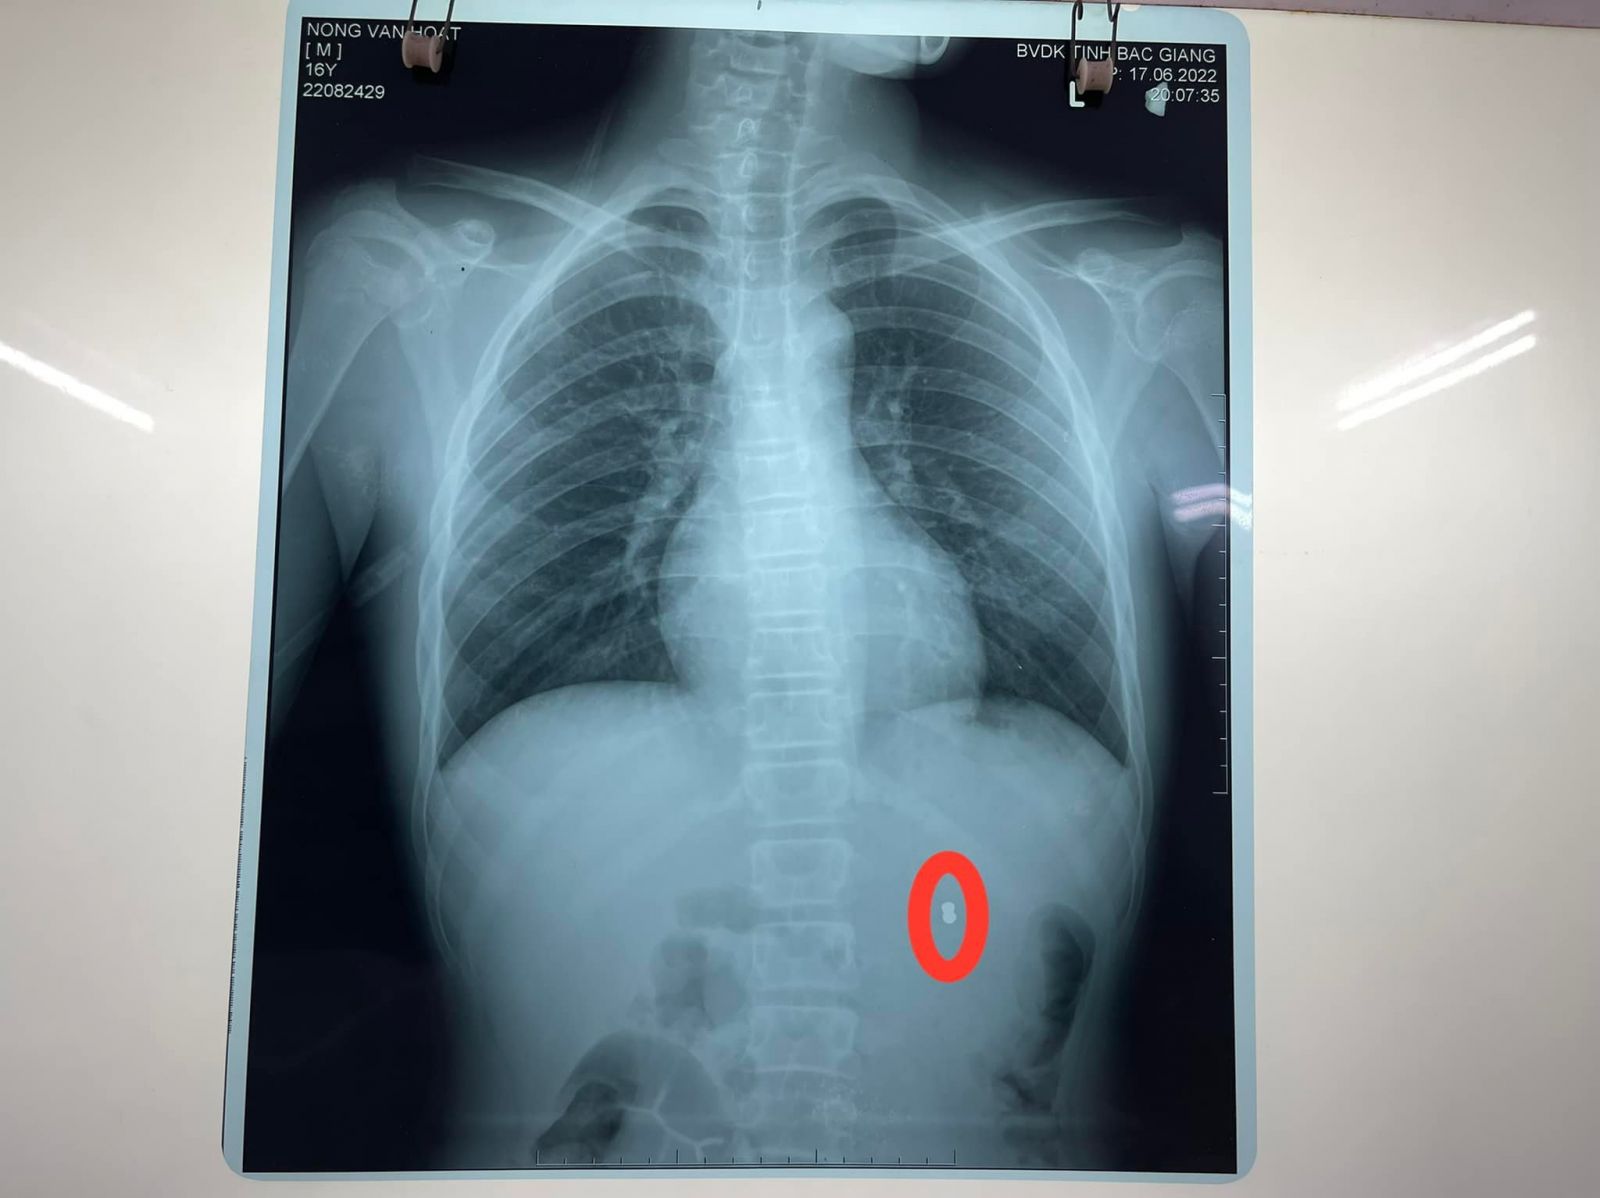

Sau khi được siêu âm, chụp CT bụng có cản quang đã phát hiện dị vật hình viên đạn trong thận trái, bệnh nhân được chuyển đến Khoa Ngoại thận tiết niệu nam học. Tại đây, các bác sĩ đã nhanh chóng hội chẩn và kết luận: bệnh nhân có vết thương thận trái cho đạn bắn, chỉ định mổ cấp cứu lấy dị vật và khâu bảo tồn thận. Kíp mổ do BsCKII Đoàn Tiến Dương, Trưởng khoa Ngoại thận tiết niệu nam học mổ chính. Ekip phẫu thuật đã thực hiện rạch vết thương thận, lấy viên đạn súng hơi ra ngoài, khâu cầm máu vết thương, làm sạch khoang quang thận đồng thời truyền 500ml máu trong cả quá trình phẫu thuật. Sau 1 giờ đồng hồ, ca phẫu thuật đã thành công, sinh tồn bệnh nhân ổn định, đầu đạn chì kích thước 0,4cmX0.7cm đã được lấy ra ngoài.

*Một số hình ảnh trong quá trình điều trị: